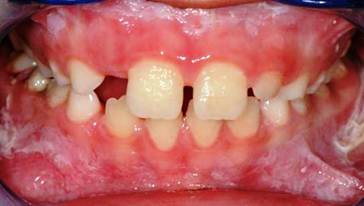

Our little patient showed an intraoral clinical condition very similar to father's, moreover, the patient was affected by a bilateral angular cheilitis. (Fig.3,4)

the little son of our patient showing white plaques developed on the gingiva.

a bilateral angular cheilitis caused by Staphylococcus aureus infection.

A buffer containing patient's saliva was submitted to a diagnostic oral microbiology laboratory: the microbiological analysis showed in the presence of Staphylococcus aureus sensitive to methicillin (MSSA) in the oral cavity of our young patient, while, no fungal infections was found.

2 rinses a day with mouthwash containing chlorhexidine digluconate at 0,12% was prescribed in order to decrease the bacteria and the occurrence of relapses of angular cheilitis.